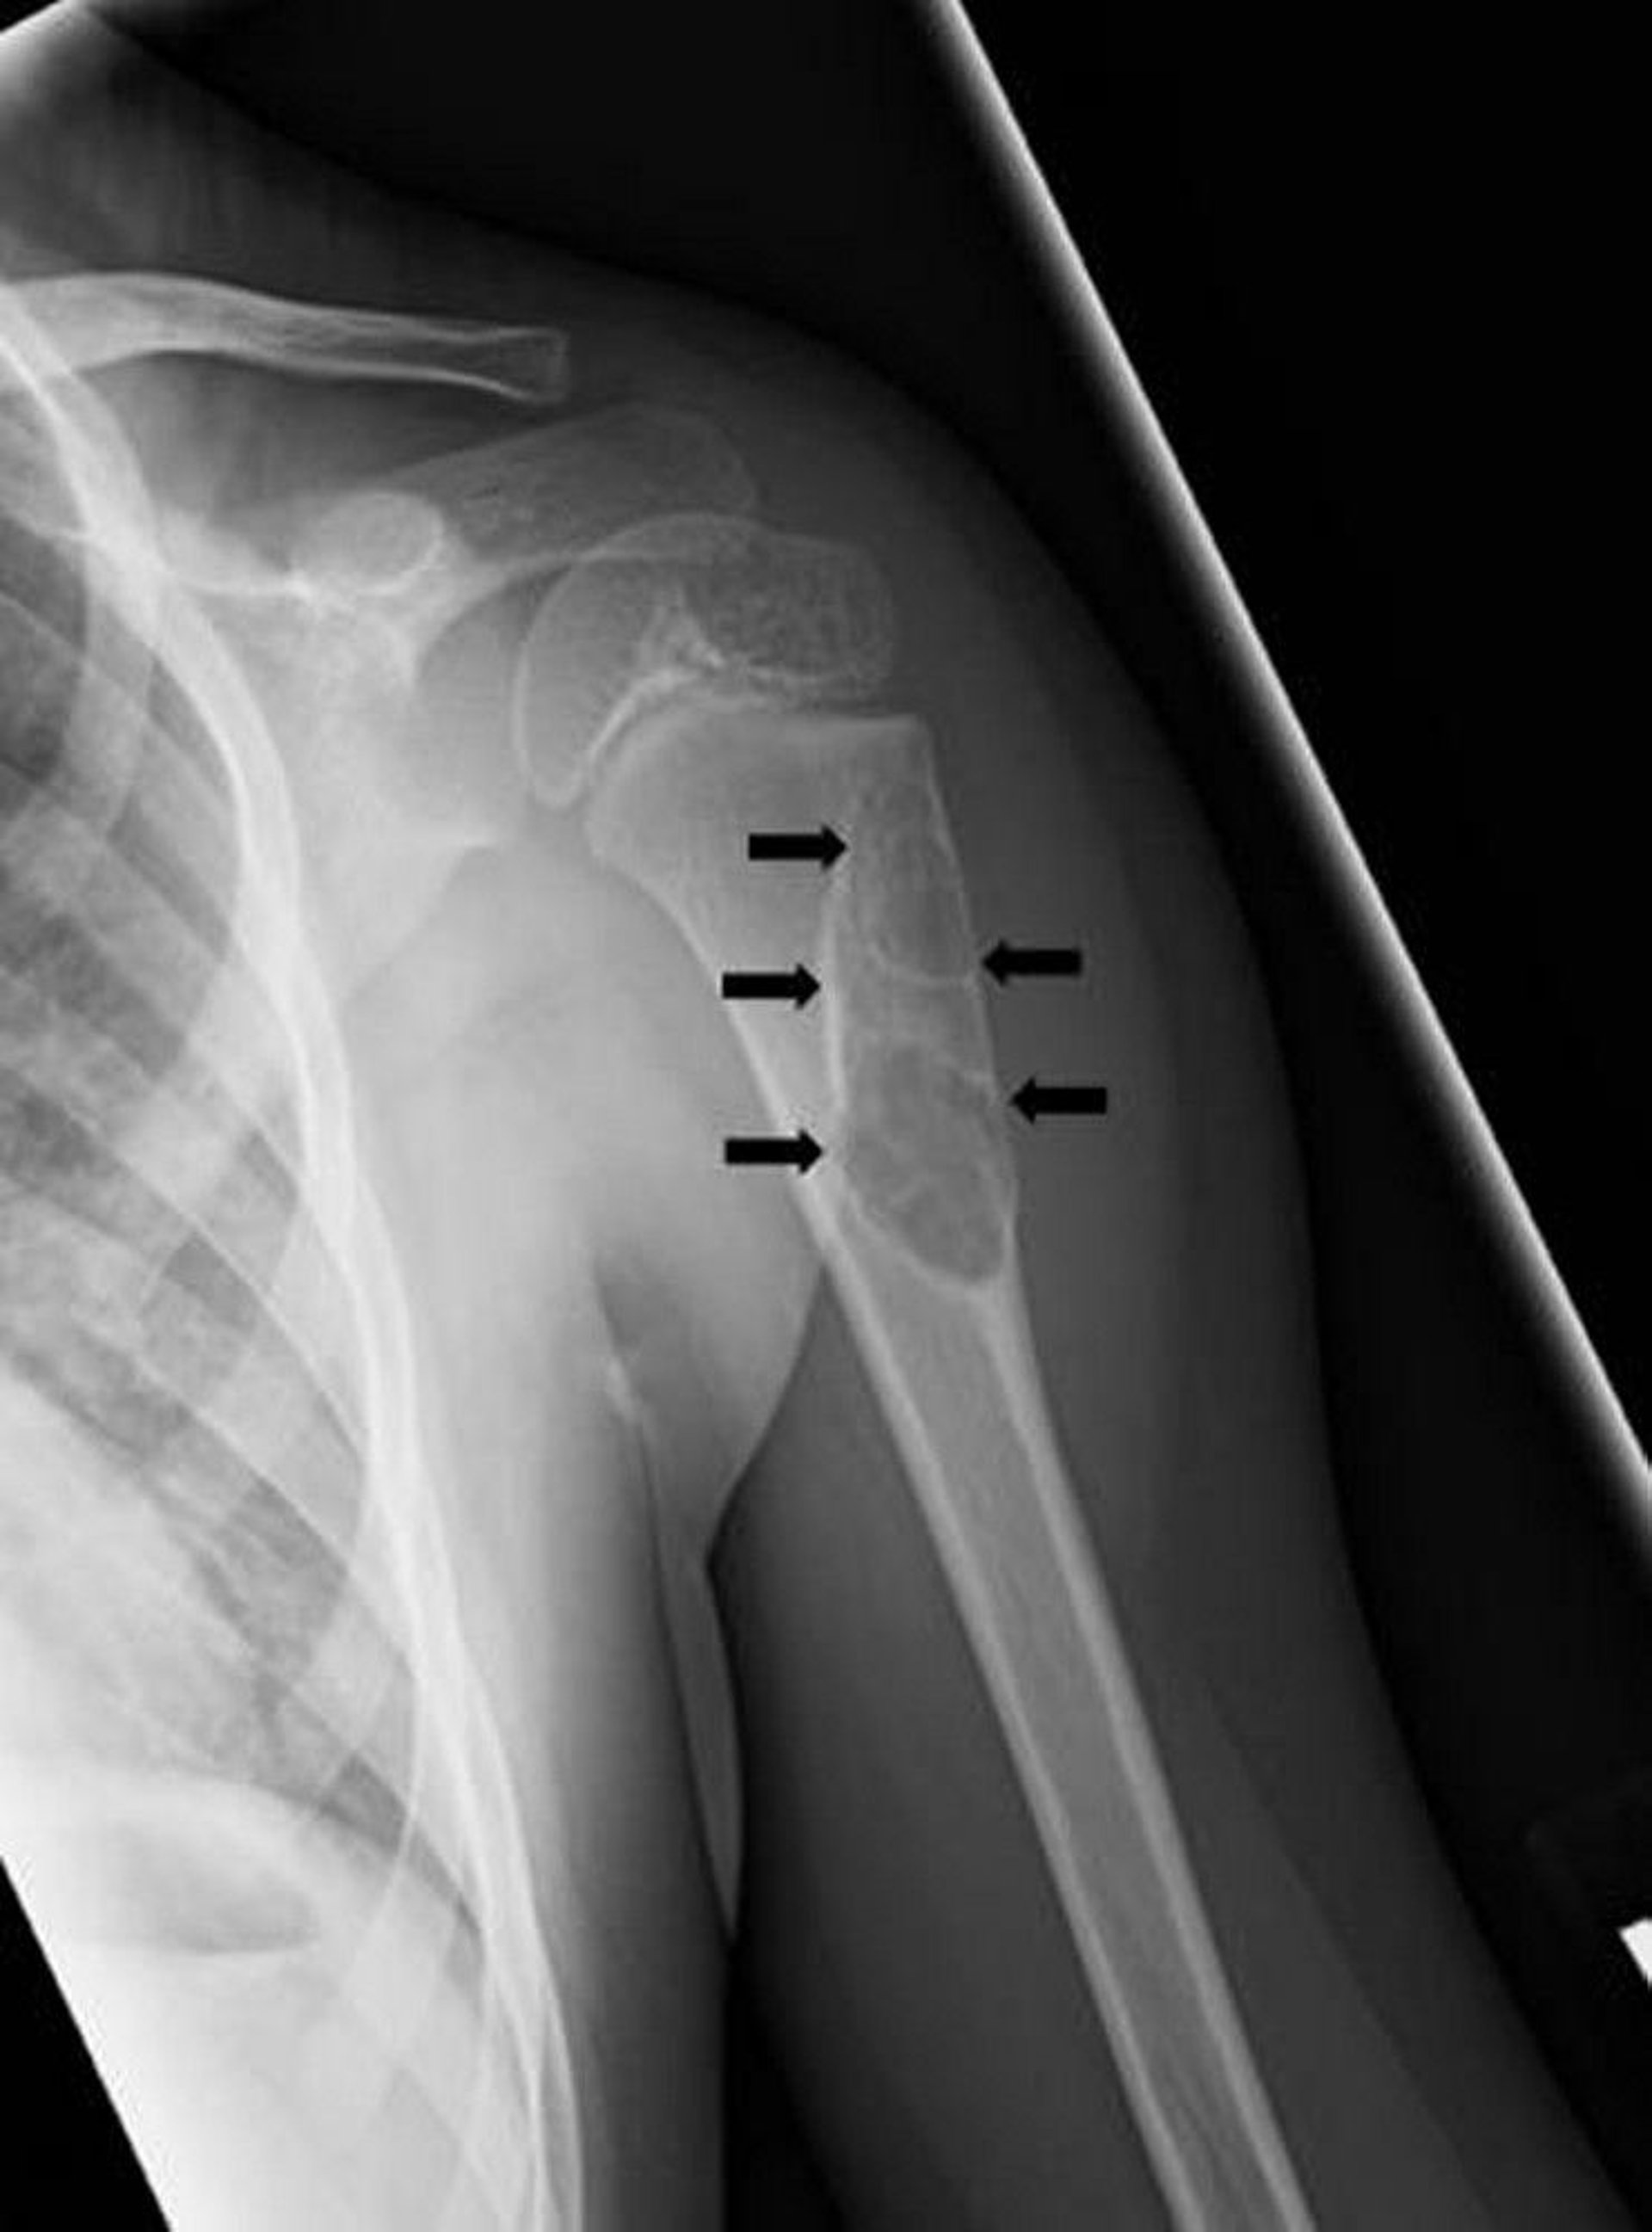

This x-ray shows a simple unicameral bone cyst (arrows) in the upper arm bone.

Image courtesy of Michael J. Joyce, MD, and Hakan Ilaslan, MD.